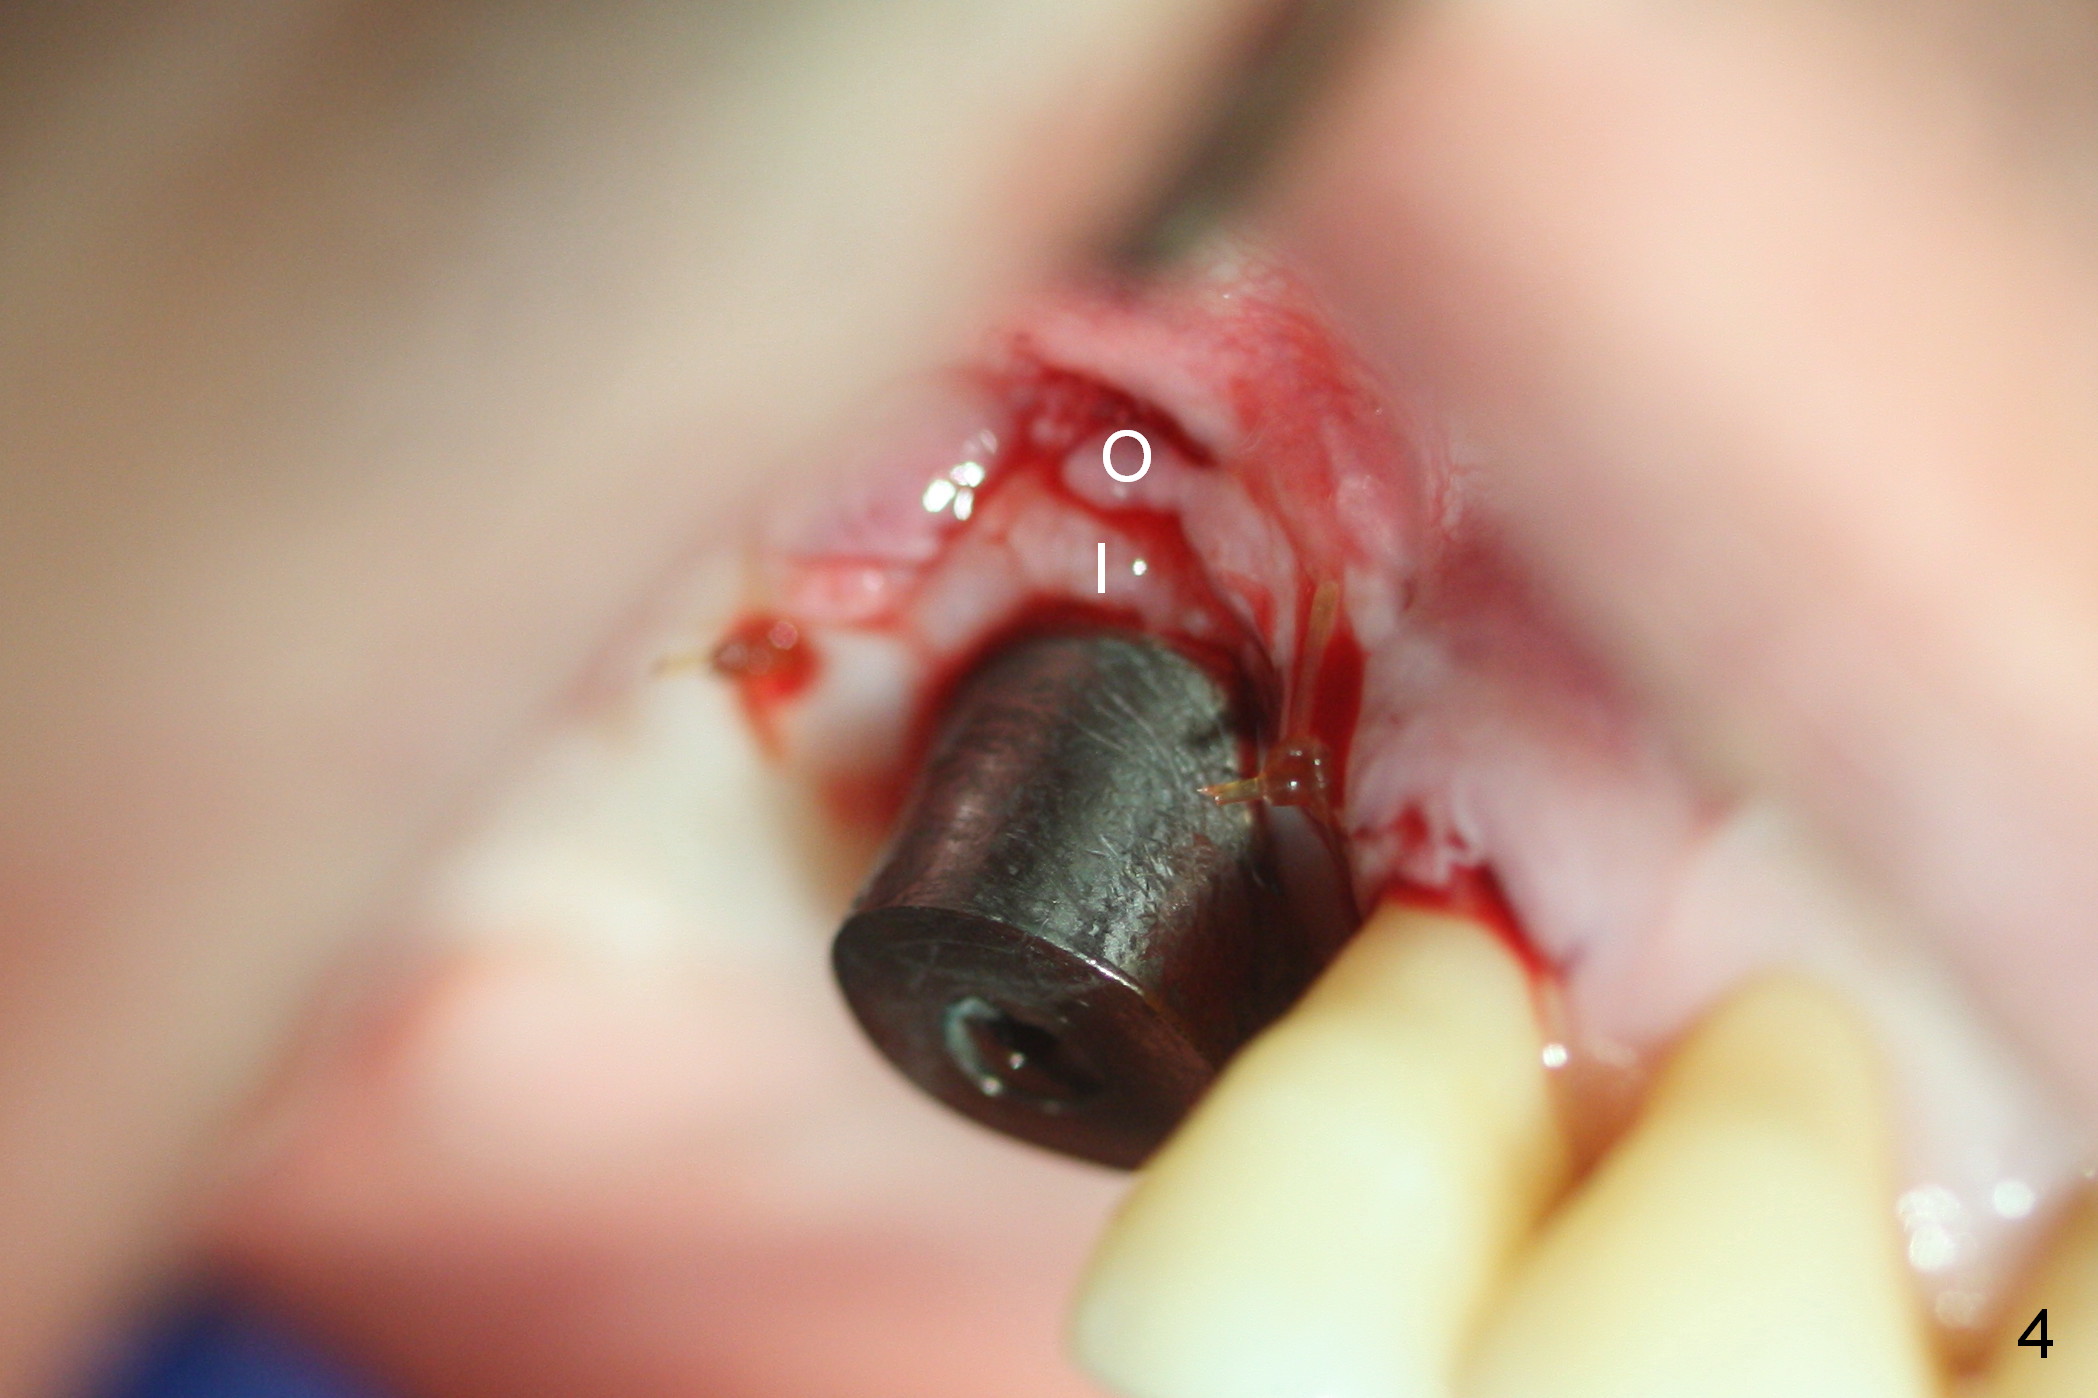

Three months post 2nd bone graft, the gingiva inside the Titanium mesh (used to be granulation tissue 1 month postop (Fig.2)) turns (Fig.3 I) as mature as the outside portion (O). When the mesh is removed, there is no thread exposure. The inner and outer portions of the gingiva are sutured later (Fig.4). The implant is restored immediately. It appears that Titanium mesh exposure is not a severe complication. If asymptomatic, leave the gingiva to heal by itself. Use small size of the mesh and release of soft tissue as much as possible may reduce the chance of mesh exposure.